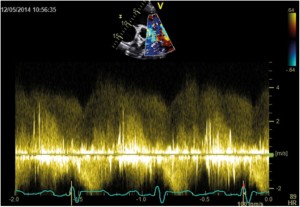

A 33-year-old man who had been diagnosed with PDA in childhood was refferedfor cardiac evaluation for fatigue and progressively worsening dyspnoea on exertion over the past 3 months. Physical examination revealed an afebrile patient, hyperdynamic precordium, a continuous murmur with thrill over the pulmonary area, peripheral oedema and hepatomegaly. The blood pressure was 120/60 mm Hg and the peripheral pulses were prominent. Auscultation of the lungs revealed mild basal crackles bilaterally. There were no clinical stigmata consistent with endocarditis. The ECG showed sinus rhythm at 78 bpm, biatrial abnormality, signs of left ventricular hypertrophy and complete right bundle branch block. There was no inflammatory syndrome or anemia. Transthoracic and transesophageal echocardiography confirmed the presence of a large PDA (defect size 11 mm), with a continuous systolic-diastolic flow signal with high velocities (up to 4.8 m/s) recorded by continuous wave Doppler examination at the level of this turbulent jet from the descending aorta to the pulmonary artery (Figures 1-3). The left ventricle was severely dilated (EDV/ESV=247/124 ml), with mild global systolic dysfunction (ejection fraction of 50%). The assessment of pulmonary artery systolic pressure was carried out by measuring peak tricuspid regurgitation velocity and the estimated value was 52 mm Hg. The TTE exam also revealed mobile vegetations on the pulmonary valve, with severe valve destructions, lack of coaptation and severe, free pulmonary regurgitation on color Doppler examination (Figures 4, 5). No vegetations were seen on the other valves, cardiac chambers or great vessels.

Figure 2. TTE examination, parasternal short-axis view; Spectral Doppler profile of continuous left-to-right ductal flow with high velocities (up to 4.8 m/s).